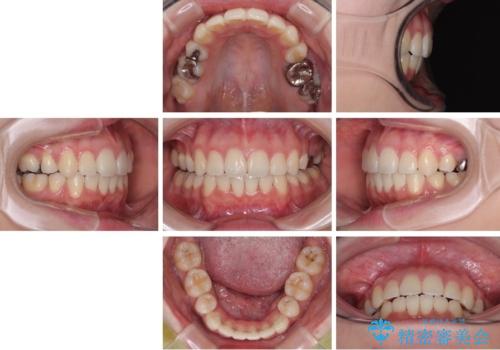

- 下の前歯のデコボコと、口元の突出感を改善したいと来院された患者様です。

突出感の強い上顎前歯をしっかりと後方移動させるため、上顎の裏側の補助装置(リンガルアーチ)とアンカースクリューを併用しています。

上下左右の第一小臼歯を抜歯して、目立ちにくいワイヤー装置で矯正を行いました。

上下の保定用マウスピースの他に、デコボコの強かった下顎前歯にはワイヤーで保定をしています。